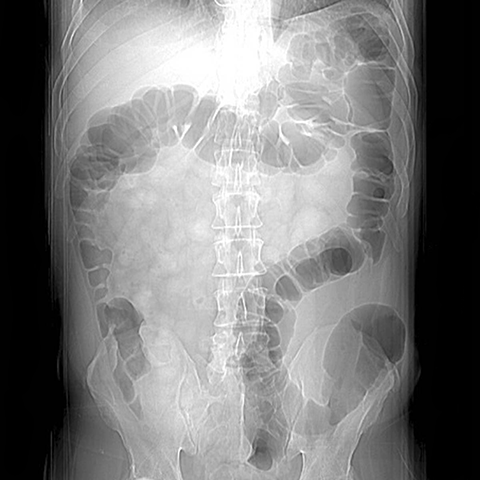

59 year-old male presents with an abdominal mass and pain. [1 of 5]